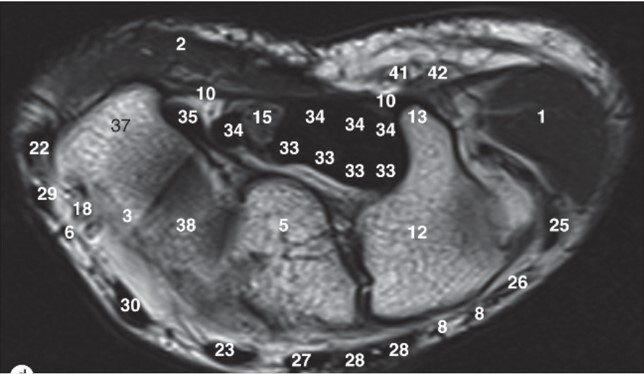

Q

Label 5,12,13,37,38

A

5=Capitate

12-Hamate

13=Hook of Hamate

37=Trapezium

38=Trapezoid